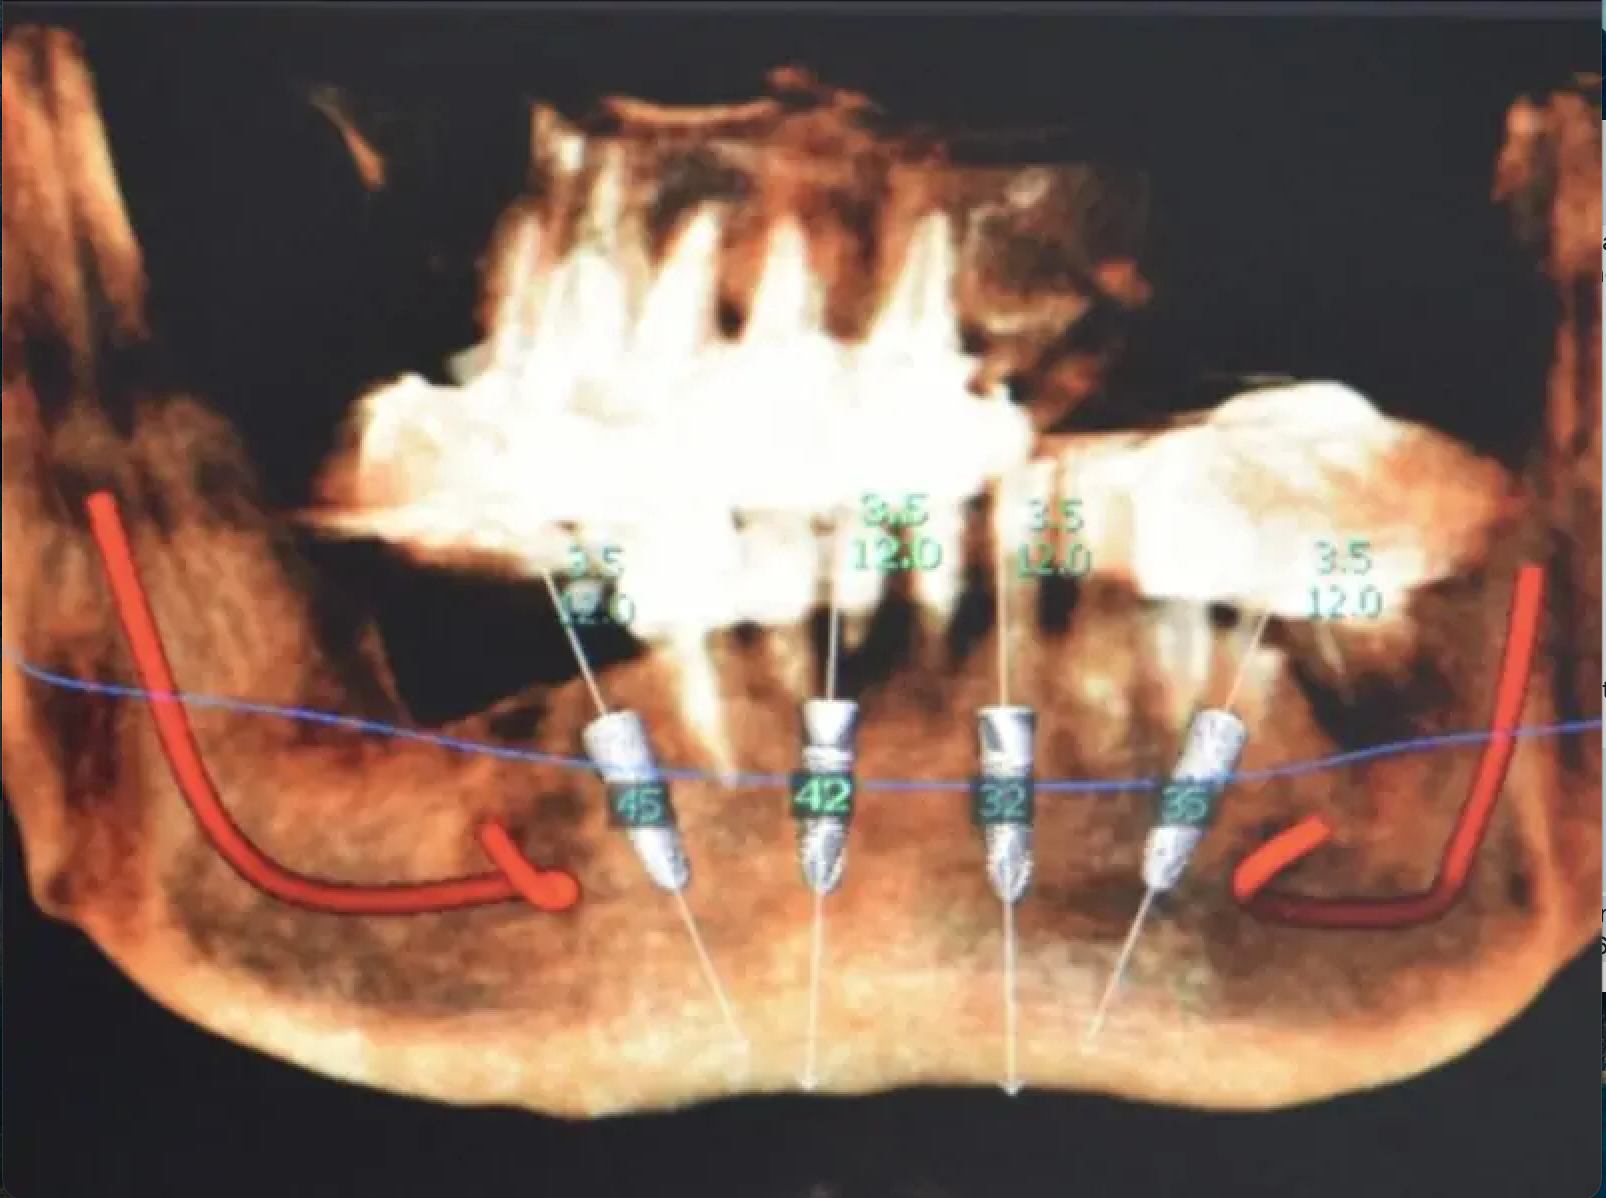

Проведении имплантации с использованием компьютерного планирования и немедленной нагрузкой на дентальные имплантаты.

Врач-стоматолог: Alessandro Preda

Лечение проведено с применением flapless-техники (бесклаптная техника) и полностью цифрового подхода: навигационная хирургия, протетическое проектирование на основе индивидуальных черт лица пациента и установление монокомпонентных имплантатов с интегрированными MUA (B&B Dental).